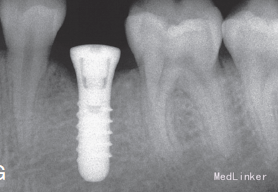

2年正畸治疗结束后,乳磨牙仍在。一年以后,患者18岁成年,拔除乳磨牙,植入植体,半年后套冠,效果很好,患者满意。有些先天缺失第二前磨牙的患者,若第二乳磨牙比较健康,可以减径后树脂修复参与正畸治疗,这样有保存骨量,维持牙弓间隙,保持与对合牙功能接触以免对合牙伸长的作用。骨量的保存利于植体的植入。